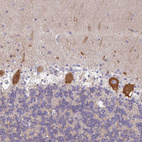

Immunohistochemical staining of human cerebellum shows strong cytoplasmic positivity in Purkinje cells.